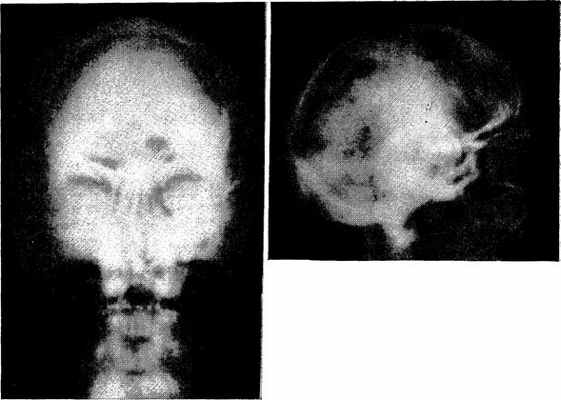

(Autosomal Dominant Osteosclerosis). С 1935 г. описано около 30 случаев утолщения кортикального слоя в диафизах длинных и коротких трубчатых костей со склеротическими изменениями в черепе, ребрах, костях таза и плечевого пояса. Martin J. Gelman из I университета в Юте [Radiology, 125, 289—296, November, 1977]. I описал 2 наблюдения генетического краниотубулярного гиперостоза, который рентгенологически близко напоминает болезнь

Ван Бухема (генерализованный кортикальный гиперостоз), хотя отличается по клиническим проявлениям и биохимическим изменениям.

Мужчина 57 лет, металлург, наблюдался по поводу упорной головной боли, болей в шее и в левом плече. В возрасте 34 лет диагностирована болезнь Педжета. Кальций, фосфор и щелочная фосфатаза сыворотки в большинстве) случаев были нормальными. Отмечены утолщение и склероз костей свода черепа (рис. 102), основания черепа, нижней челюсти, ключиц, лопаток и ребер (рис. 103). Склероз поражал также латеральные и задние элементы позвоночника и подвздошных костей (рис. 104). Наблюдалось утолщение коркового слоя плечевых, бедренных и большеберцовых костей и цилиндрическая форма диафизов большеберцовых костей (рис. 105). При биопсии правого акромиона и правой подвздошной кости обнаружена нормальная утолщенная зрелая пластинчатая кость. Произведен спондилодез C4—C7, не приведший к клиническому улучшению.

Рис. 102. Утолщение свода черепа, наиболее выраженное в базальной части и в области височных костей. Остаточное интракраниальное скопление пантопака после миелографии